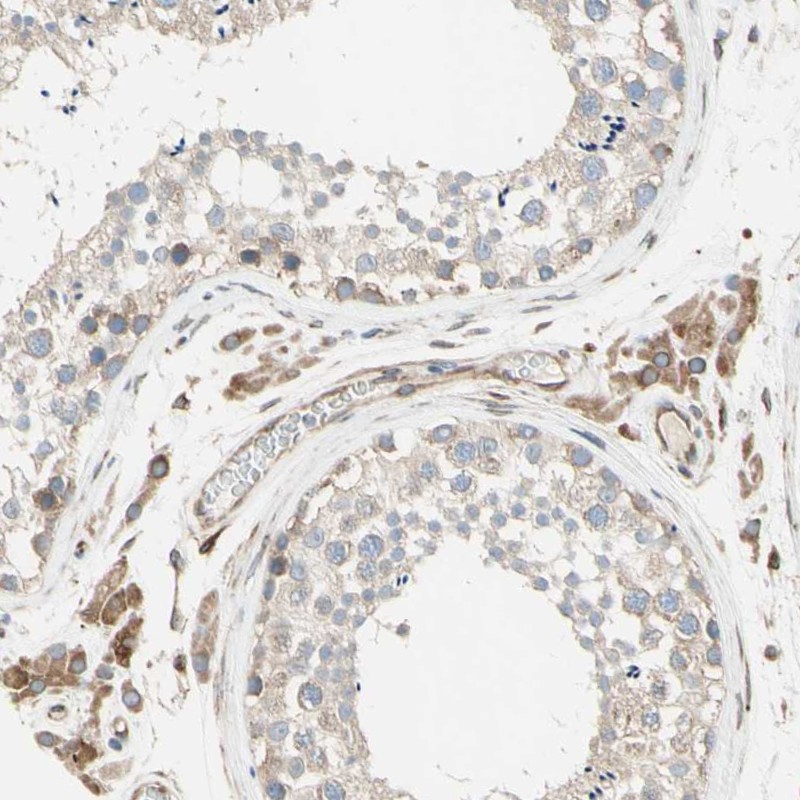

Immunohistochemical staining of human testis shows cytoplasmic positivity in cells in seminiferous ducts and Leydig cells.